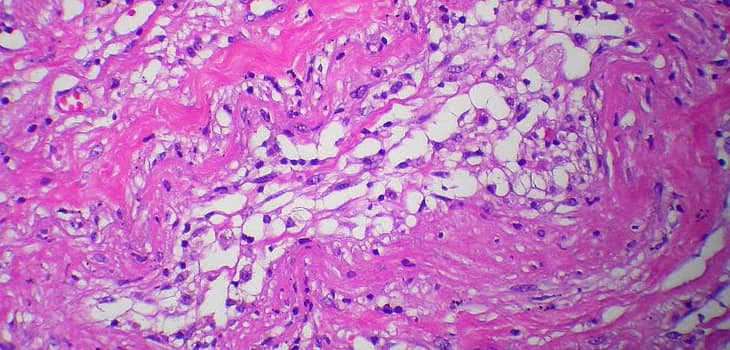

Cos'è il Lipogems? Lipogems è una tecnologia innovativa che consente di processare in un sistema completamente chiuso anche quantità minime di tessuto adiposo,...